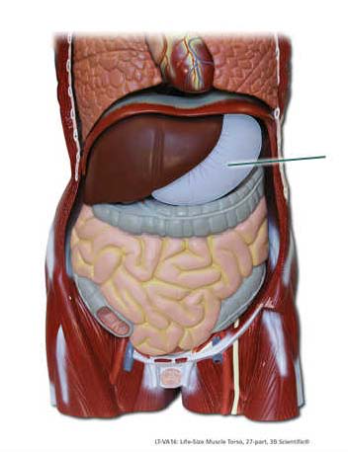

Into which organ does the highlighted structure empty?

stomach

Identify the highlighted structure.

stomach

The highlighted structure separates the stomach from the…

duodenum